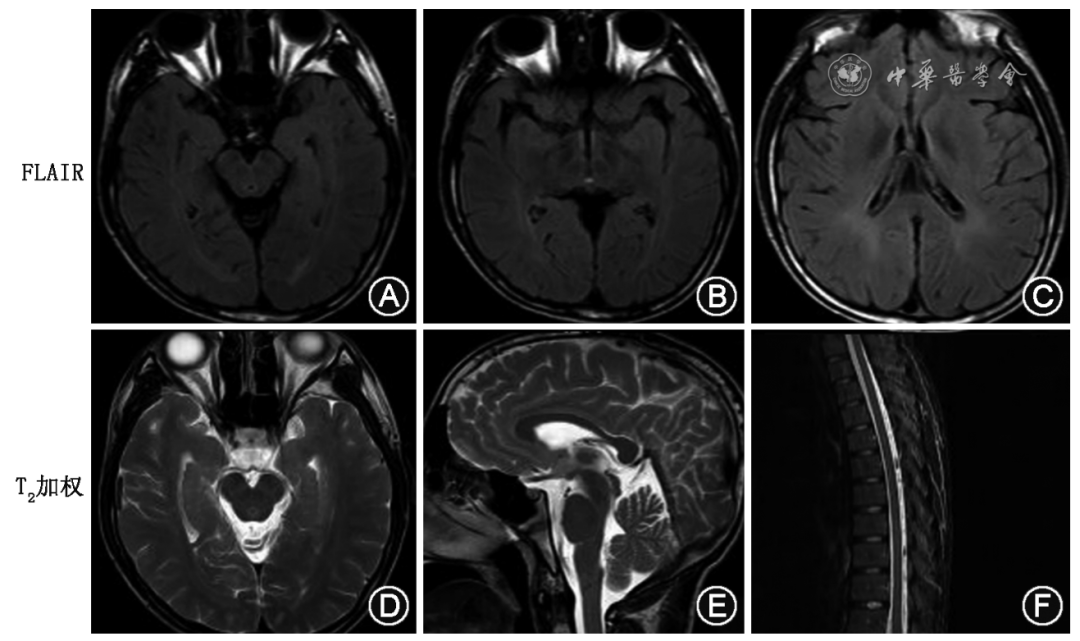

先证者头颅MRI示:在FLAIR像见中脑导水管、第三脑室周围和侧脑室旁白质信号增高(图2A~C)。T2加权像示四叠体池及脚尖窝增宽,胼胝体可疑变薄,胸段脊髓可疑变细(图2 D~F)。

图2  尼曼-匹克病C型先证者头颅磁共振成像。在液体衰减反转恢复(FLAIR)像(A~C)见中脑导水管、第三脑室周围和侧脑室旁脑白质信号增高。T2加权像示四叠体池及脚尖窝增宽,胼胝体可疑变薄(D、E),胸段脊髓可疑变细表现(F)

Figure 2  Brain magnetic resonance imaging of the proband with Niemann-Pick disease type C. Increased signal intensity of white matter around the lateral ventricle, the mesencephalic aqueduct and periphery of the third ventricle was shown on fluid attenuated inversion recovery (FLAIR) images (A-C). T2-weighted imaging showed widening of the quadrigeminal cistern and apex fossa, suspicious thinning of the corpus callosum (D,E), and suspicious thinning of the thoracic spinal cord (F)

本家系中的2例患者,起病年龄和临床表型有很大的差异,这与既往的研究报道一致,NPC具有显著的临床和遗传异质性[2]。据报道,NPC的主要临床特征包括小脑性共济失调、垂直核上性眼肌麻痹、构音障碍、认知障碍、运动障碍、脾肿大、精神障碍和吞咽困难,较不常见的症状为癫痫、猝倒和皮质肌阵挛发作等[8, 9, 10, 11, 12, 13]。垂直性核上性凝视麻痹是NPC具有特征性的临床表现之一,临床医生应加强对此体征的识别,有助于为NPC早期诊断提供有用的线索[10,14, 15]。本研究中的2例患者都有明确垂直性眼球活动障碍,尤其是下视受限明显。先证者头颅MRI提示中脑导水管、第三脑室周围白质的异常信号,四叠体池和脚尖窝的增宽提示中脑萎缩可能,这可能是导致患者出现垂直性核上性麻痹的原因。先证者侧脑室旁脑白质的信号异常,胼胝体变薄和脊髓的变细可能与患者的认知障碍、锥体束受损、共济失调、构音障碍相关。先证者的脑白质信号的异常和胼胝体变薄与既往的报道一致[3,16],但无特异性,对诊断帮助不大。NPC除有神经系统受累外,常伴有内脏系统受累表现,如肝脾肿大和间质性肺炎等[17],骨髓、肝、脾、肺等组织病理检查发现富含脂质的巨噬细胞,也称泡沫样细胞或尼曼-匹克细胞有助于诊断。近年来,血浆壳三糖苷酶、7-酮胆固醇、胆甾醇-3β、5α、6β-三羟基胆酰甘氨酸和胆汁酸等已成为 NPC特异性生物诊断标志物,但基因检查仍被认为是NPC确诊的有效手段,并可以和其他遗传代谢性疾病相鉴别[18, 19, 20]。如先证者铜蓝蛋白降低,但眼科裂隙灯检查未看见K-F环,基因检测未发现ATP7B基因的致病突变,可排除肝豆状核变性;先证者体格检查可见锥体束征、高足弓、马蹄内翻足畸形,MRI显示胼胝体可疑变薄、胸段脊髓可疑变细表现,临床需要与伴有变薄胼胝体的遗传性痉挛性截瘫进行鉴别,但基因检测并未发现遗传性痉挛性截瘫的致病基因,可排除该病。NPC的确诊需要临床医师进行详细的病史询问、细致的体格检查,一旦临床怀疑NPC,可通过生物标志物检测、骨髓穿刺活组织检查、皮肤成纤维细胞filipin染色和基因检测进行确诊。正如本家系中的先证者一样,以麦格司他为代表的药物治疗是成功的,服用麦格司他治疗1年后,先证者的神经症状有明显的改善。但不幸的是,该药目前价格仍然较贵,虽然已经进入国家的谈判药系列,报销比例已经大幅提高,但很多家庭仍无力承担,先证者弟弟因为经济原因一直未服药治疗。除麦格司他外,环糊精、双嘧达莫、N-乙酰-L-亮氨酸和阿莫洛莫在相应的临床试验中也显示出有效性和安全性[15,21, 22]。